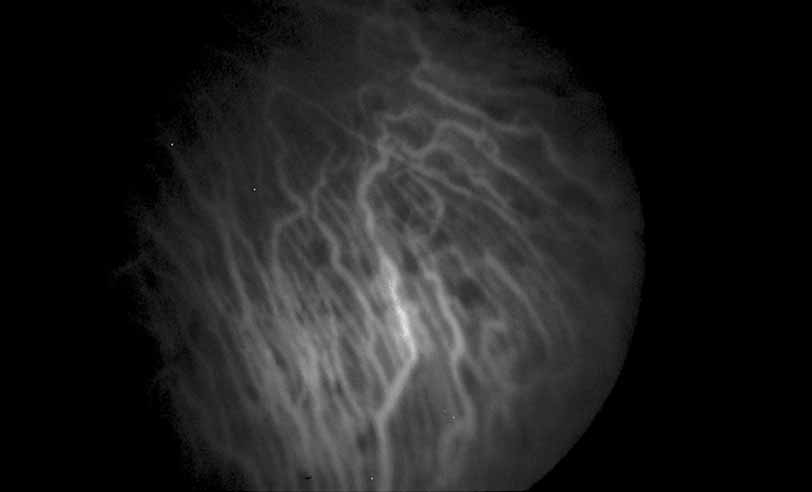

In addition to exudative detachment of the neurosensory retina and papillitis, patients with Vogt-Koyanagi-Harada disease as well as sympathetic ophthalmia may also develop serous detachment of the retinal pigment epithelium. This differs from the usual form of retinal pigment epithelium detachment that occurs in age-related macular degeneration by the absence of adjacent soft drusen and the presence of multiple pinpoint leak sites and disc staining characteristic of Vogt-Koyanagi-Harada disease (see Figs. 30, 31, 32, 33, and 34) and sympathetic ophthalmia (see Figs. 35 and 36).41–46 In cases of Vogt-Koyanagi-Harada disease with serous retinal detachment or detachment of the retinal pigment epithelium, some authors have reported hyperfluorescence of the large choroidal vessels in early stages of the angiogram, followed by dye leakage in the late phase of the study, whereas others report leakage from the choroidal vessels throughout the study (see Figs. 33 and 34).11,12

Fig. 33 Vogt-Koyanagi-Harada syndrome. Early ICG angiography shows hyperfluorescence of the large choroidal vessels in the central macula.

Fig. 34 Vogt-Koyanagi-Harada syndrome. Later frames of the ICG show a large plaque of hyperfluorescence.